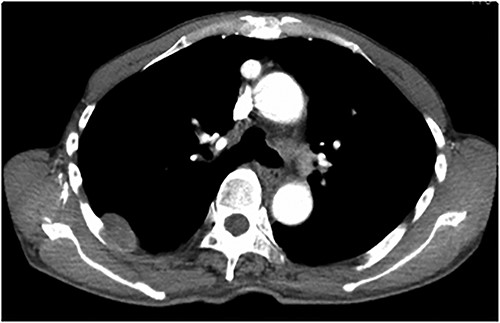

An asymptomatic 79-year-old male who was diagnosed with a chest wall tumor, which had been detected by an X-ray of a health examination, presented to our hospital for surgical intervention. He had no relevant past medical history, including malignant neoplasm or radiation therapy. No mass was palpable. The chest X-ray revealed a tumor shadow of 3 cm in diameter in the right upper lung field (Fig. 1). Chest contrast computed tomography (CT) revealed a well-circumscribed tumor shadow measuring 37 × 27 mm in the posterolateral region of the right sixth intercostal space, the size of which had increased 1.5 times in the previous 3 months (Fig. 2). Thoracic magnetic resonance imaging (MRI) revealed a solid tumor that was enhanced by gadolinium on T1-weighted imaging (T1WI). T2-weighted imaging (T2WI) showed a homogeneous mass with iso-intensity. The tumor was inhomogeneous while demonstrating a maximum standardized uptake value (SUV) of the [18F]-2-deoxy-D-glucose (FDG) uptake under positron emission tomography (PET), with a range of 3.4–4.1 (Fig. 3). There was no significant uptake at other sites, including the mediastinal lymph nodes. No tumor-markers (CEA, proGRP and CYFRA) were detected in a laboratory analysis. Based on these examinations, we suspected a neurogenic tumor, especially schwannoma, and we opted for surgical resection. Considering the fact that ~10% of neurogenic tumors are malignant and the FDG uptake was heterogeneous, we planned to perform an intraoperative frozen section examination. We first performed tumor resection. The operation was performed in the left lateral position under general anesthesia. A 30° viewing angle thoracoscope was set at the middle axillary line of the seventh intercostal space. The tumor was smooth, slightly solid and covered with pleura (Fig. 4). We added a 4-cm incision just above the tumor, while verifying its location through the thoracoscope, and easily removed it from the chest wall. The tumor was diagnosed as sarcoma based on the frozen section examination. Therefore, we added removal of a portion of the sixth and seventh right rib. We excised the chest wall with a 2-cm margin from the lesion, confirming an adequate length through the thoracoscope. Chest wall reconstruction was performed with DUALMESH® (Gore, Flagstaff, AZ). On the cut section, the tumor appeared as solid, smooth-surfaced and encapsulated whitish mass of 3.7 × 2.7 cm in size. Upon microscopic examination, the tumor was composed of fascicles of highly atypical spindle cells mitotic figures exceeding 15 per 10 high-power fields. Immunohistochemistry was positive for αSMA (Fig. 5), desmin and caldesmon and was negative for S-100 protein (data not shown). All margins were negative, and no invasion to the peripheral organs was seen. We concluded that the tumor was leiomyosarcoma of the chest wall. He was discharged on post-operative day 10 without any complications. Since we considered that curative resection had been achieved, no adjuvant therapy was performed. He is still being followed up; however, liver and multiple lung metastases were detected at 5 years after surgery.